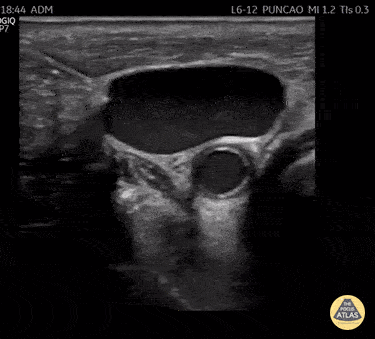

Insertion of central venous catheter by ultrasound-guided seldinger technique. In this View obtained with a linear Probe on the oblique axis of the internal jugular vein, we observed in-plane the advance of the needle during venous puncture and also the beginning of the passage of the guidewire. POCUS is a key tool to increase the safety of this procedure. @R_Tambelli